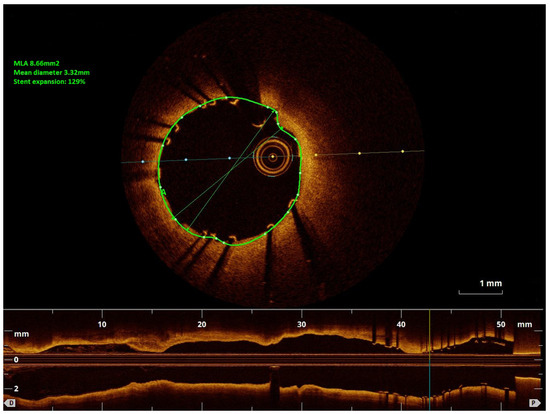

Impressive Late Stent Recoil of a Drug-Eluting Resorbable Magnesium Coronary Stent

Case description